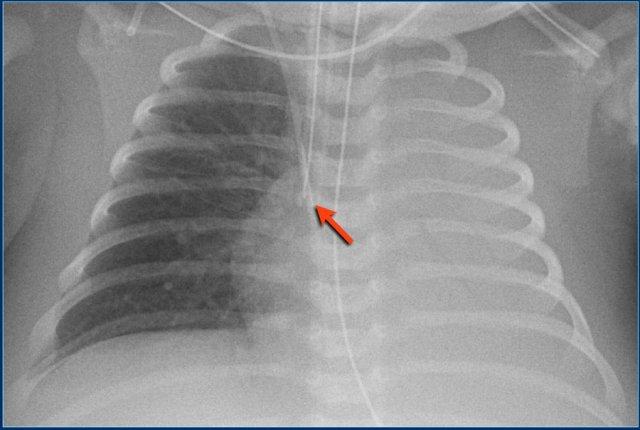

Đường truyền động mạch rốn (3)

Các phát hiện bao gồm:

- Đặt sai vị trí đường truyền động mạch rốn, bị gấp khúc trong lòng động mạch chủ bụng.